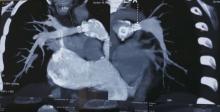

Featured Image:

This video shows the reconstruction of the pulmonary artery in an 8-year-old girl, who had undergone repair of truncus arteriosus at the age of one. The patient presented with Class II/III dyspnea, and CT imaging revealed that the conduit and stent were severely calcified and stenosed. The conduit and branch were replaced and the pulmonary artery was reconstructed.